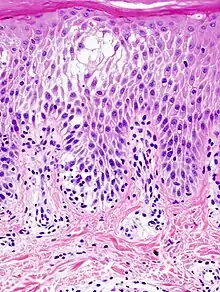

Spongiosis is mainly intercellular[1] edema (abnormal accumulation of fluid) in the epidermis,[2] and is characteristic of eczematous dermatitis, manifested clinically by intraepidermal vesicles (fluid-containing spaces), "juicy" papules, and/or lichenification.[3] It is a severe case of eczema that affects the epidermis, dermis or subcutaneous skin tissues.[4] The three types of spongiotic dermatitis are acute, subacute and chronic.[4] A dermatologist can diagnose acute spongiotic dermatitis by examining the skin during an office visit, but a biopsy is needed for an accurate diagnosis of the type.